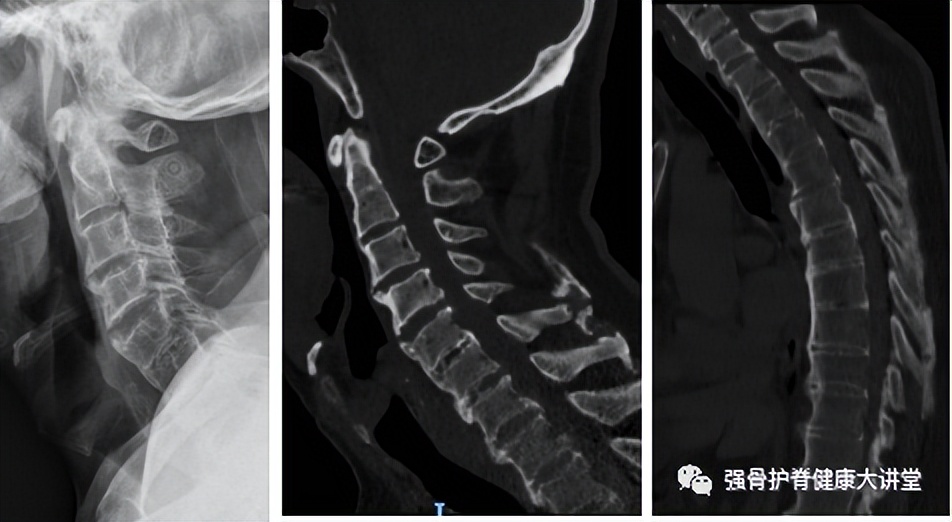

下面分享我院治疗的76岁老年男性,因头晕摔倒后出现颈椎骨折,患者入院时四肢肌力1-2级,大小便*禁失**;手术后1月四肢肌力恢复至3-4级,小便正常,大便稍无力。

脊柱竹节样改变,C3-6层面相应椎管狭窄。